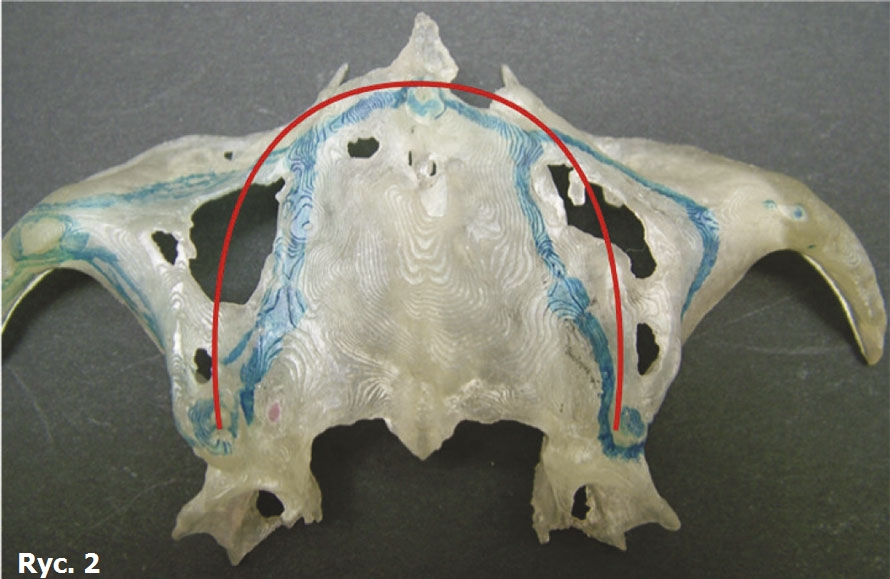

Pacjentka sprawia wrażenie przygnębionej i podkreśla, że obecnie prowadzi zakonny tryb życia, stroniąc od jakichkolwiek kontaktów międzyludzkich z powodu nadmiernie luźnej i bardzo niestabilnej protezy górnej. Jedynym sposobem na wyraźną wymowę jest u niej wyjęcie protezy przed rozmową. Zdecydowanie sprzeciwia się poddaniu kolejnym zabiegom regeneracyjnym i wykonaniu przeszczepów kości. Wyniki badania TK oraz analiza modeli stereolitograficznych pacjentki ukazują katastrofalny zanik wyrostków zębodołowych szczęki (ryc. 2). Czerwona linia na sklepieniu podniebienia jest całkowicie płaska i wskazuje lokalizację prawidłowej okluzji centralnej, gdyby jeszcze istniał wyrostek zębodołowy, do którego byłoby możliwe wszczepienie implantów śrubowych.